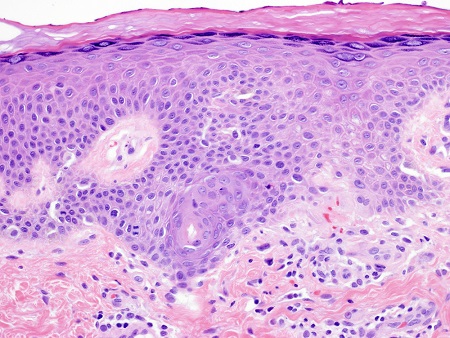

Haematoxylin- and eosin-stained sections from a lesion of miliaria rubra demonstrates spongiosis of an intra-epidermal sweat duct, sometimes forming a spongiotic vesicle, with lymphocytic exocytosis and a superficial perivascular infiltrate of lymphocytes and neutrophils.

[Figure caption and citation for the preceding image starts]: Photomicrograph of miliaria rubra showing intra-epidermal acrosyringeal spongiosis and underlying chronic inflammation (H&Ex400)From Brian L. Swick's collection, used with permission [Citation ends].